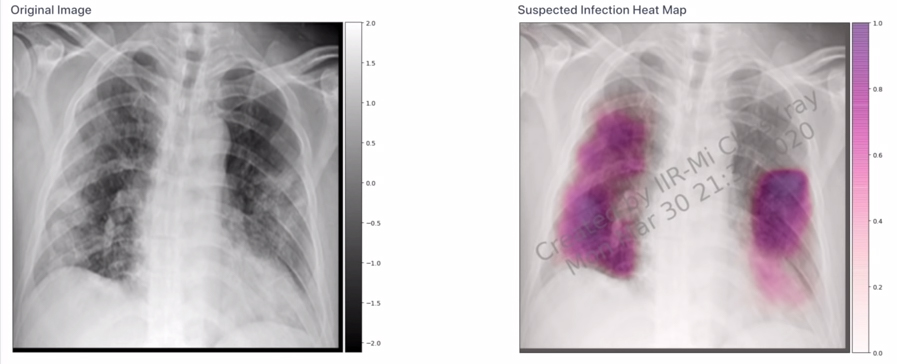

▼成大五人團隊研發出以AI人工智慧判讀肺部X光片,原本需要人工「40分鐘」判讀的過程,AI只消「1秒」就能判讀是否具有新冠特徵,讓醫師能更快下醫療決策。蔣榮先開心表示:「在網站上看見國旗,真是太令人興奮了」,並強調「MedCheX」系統檢測準確率高達92%,對此團隊決定「全球免費使用」。團隊參加的是競爭很大的「醫療科技類」,能獲選是莫大的成就。